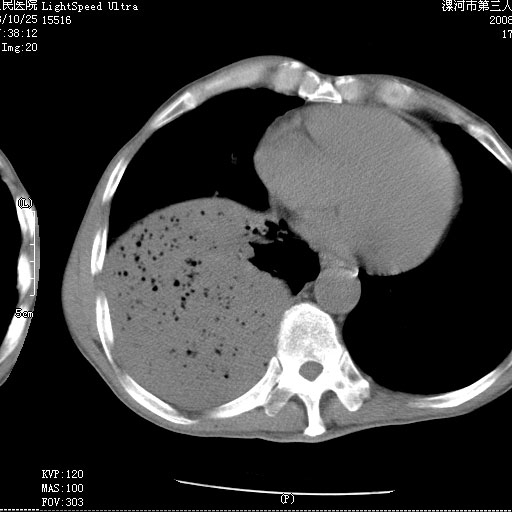

m 老年 发烧、呼吸困难,慢支、肺气肿多年;记的那次是下午大概17:38做的,晚上窒息死亡。

上面的层面就慢性支气管炎肺气肿、肺大泡,别的没有什么、也就不传了。

当时我怀疑:1、阻塞性肺不张早期 2、肺脓肿早期,望老师们发表意见

3、细支气管肺泡癌可以排除,病变以斜裂为界,呈大片状高密度影,内可见多发小气泡,表明有产气杆菌感染所致,内无明显的支气管“枯树枝征”表现,再结合其临床改变(细支气管肺泡癌临表表现重、影像表现轻)所以不符合细支气管肺泡癌(炎症型)的改变。

病变按肺叶分布,病变内可见多个小空腔影,未见充气支气管影,中间段支气管管腔肺窗示密度欠均匀,下肺支气管分叉处基底段支气管隐约可见,未见明显狭窄,中叶支气管通畅,

考虑:阻塞性肺炎伴小脓肿形成可能性大。(痰栓可能性大)

右下肺实变,内有弥漫分面小气泡而无支气管征,叶间裂前移,呈臌大之形,而无收缩之状,兼纵隔稍左行移,故。不支持不张,倒支持大叶肺叶,如楼上所说,小气泡不象残留之肺,不可以考虑产气菌感染吗。

阻塞性肺炎,肺脓肿形成。依据,右下支气管不通,大片实变形内可见小气泡。不支持肺不张。